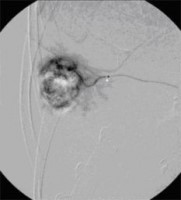

« Zurück Superselektive transarterielle Chemoembolisation (TACE) mit Sondierung eines tumorversorgenden Gefäßes 2 (Bild 4 von 5) Vorwärts »

« Zurück Superselektive transarterielle Chemoembolisation (TACE) mit Sondierung eines tumorversorgenden Gefäßes 3 (Bild 5 von 5)